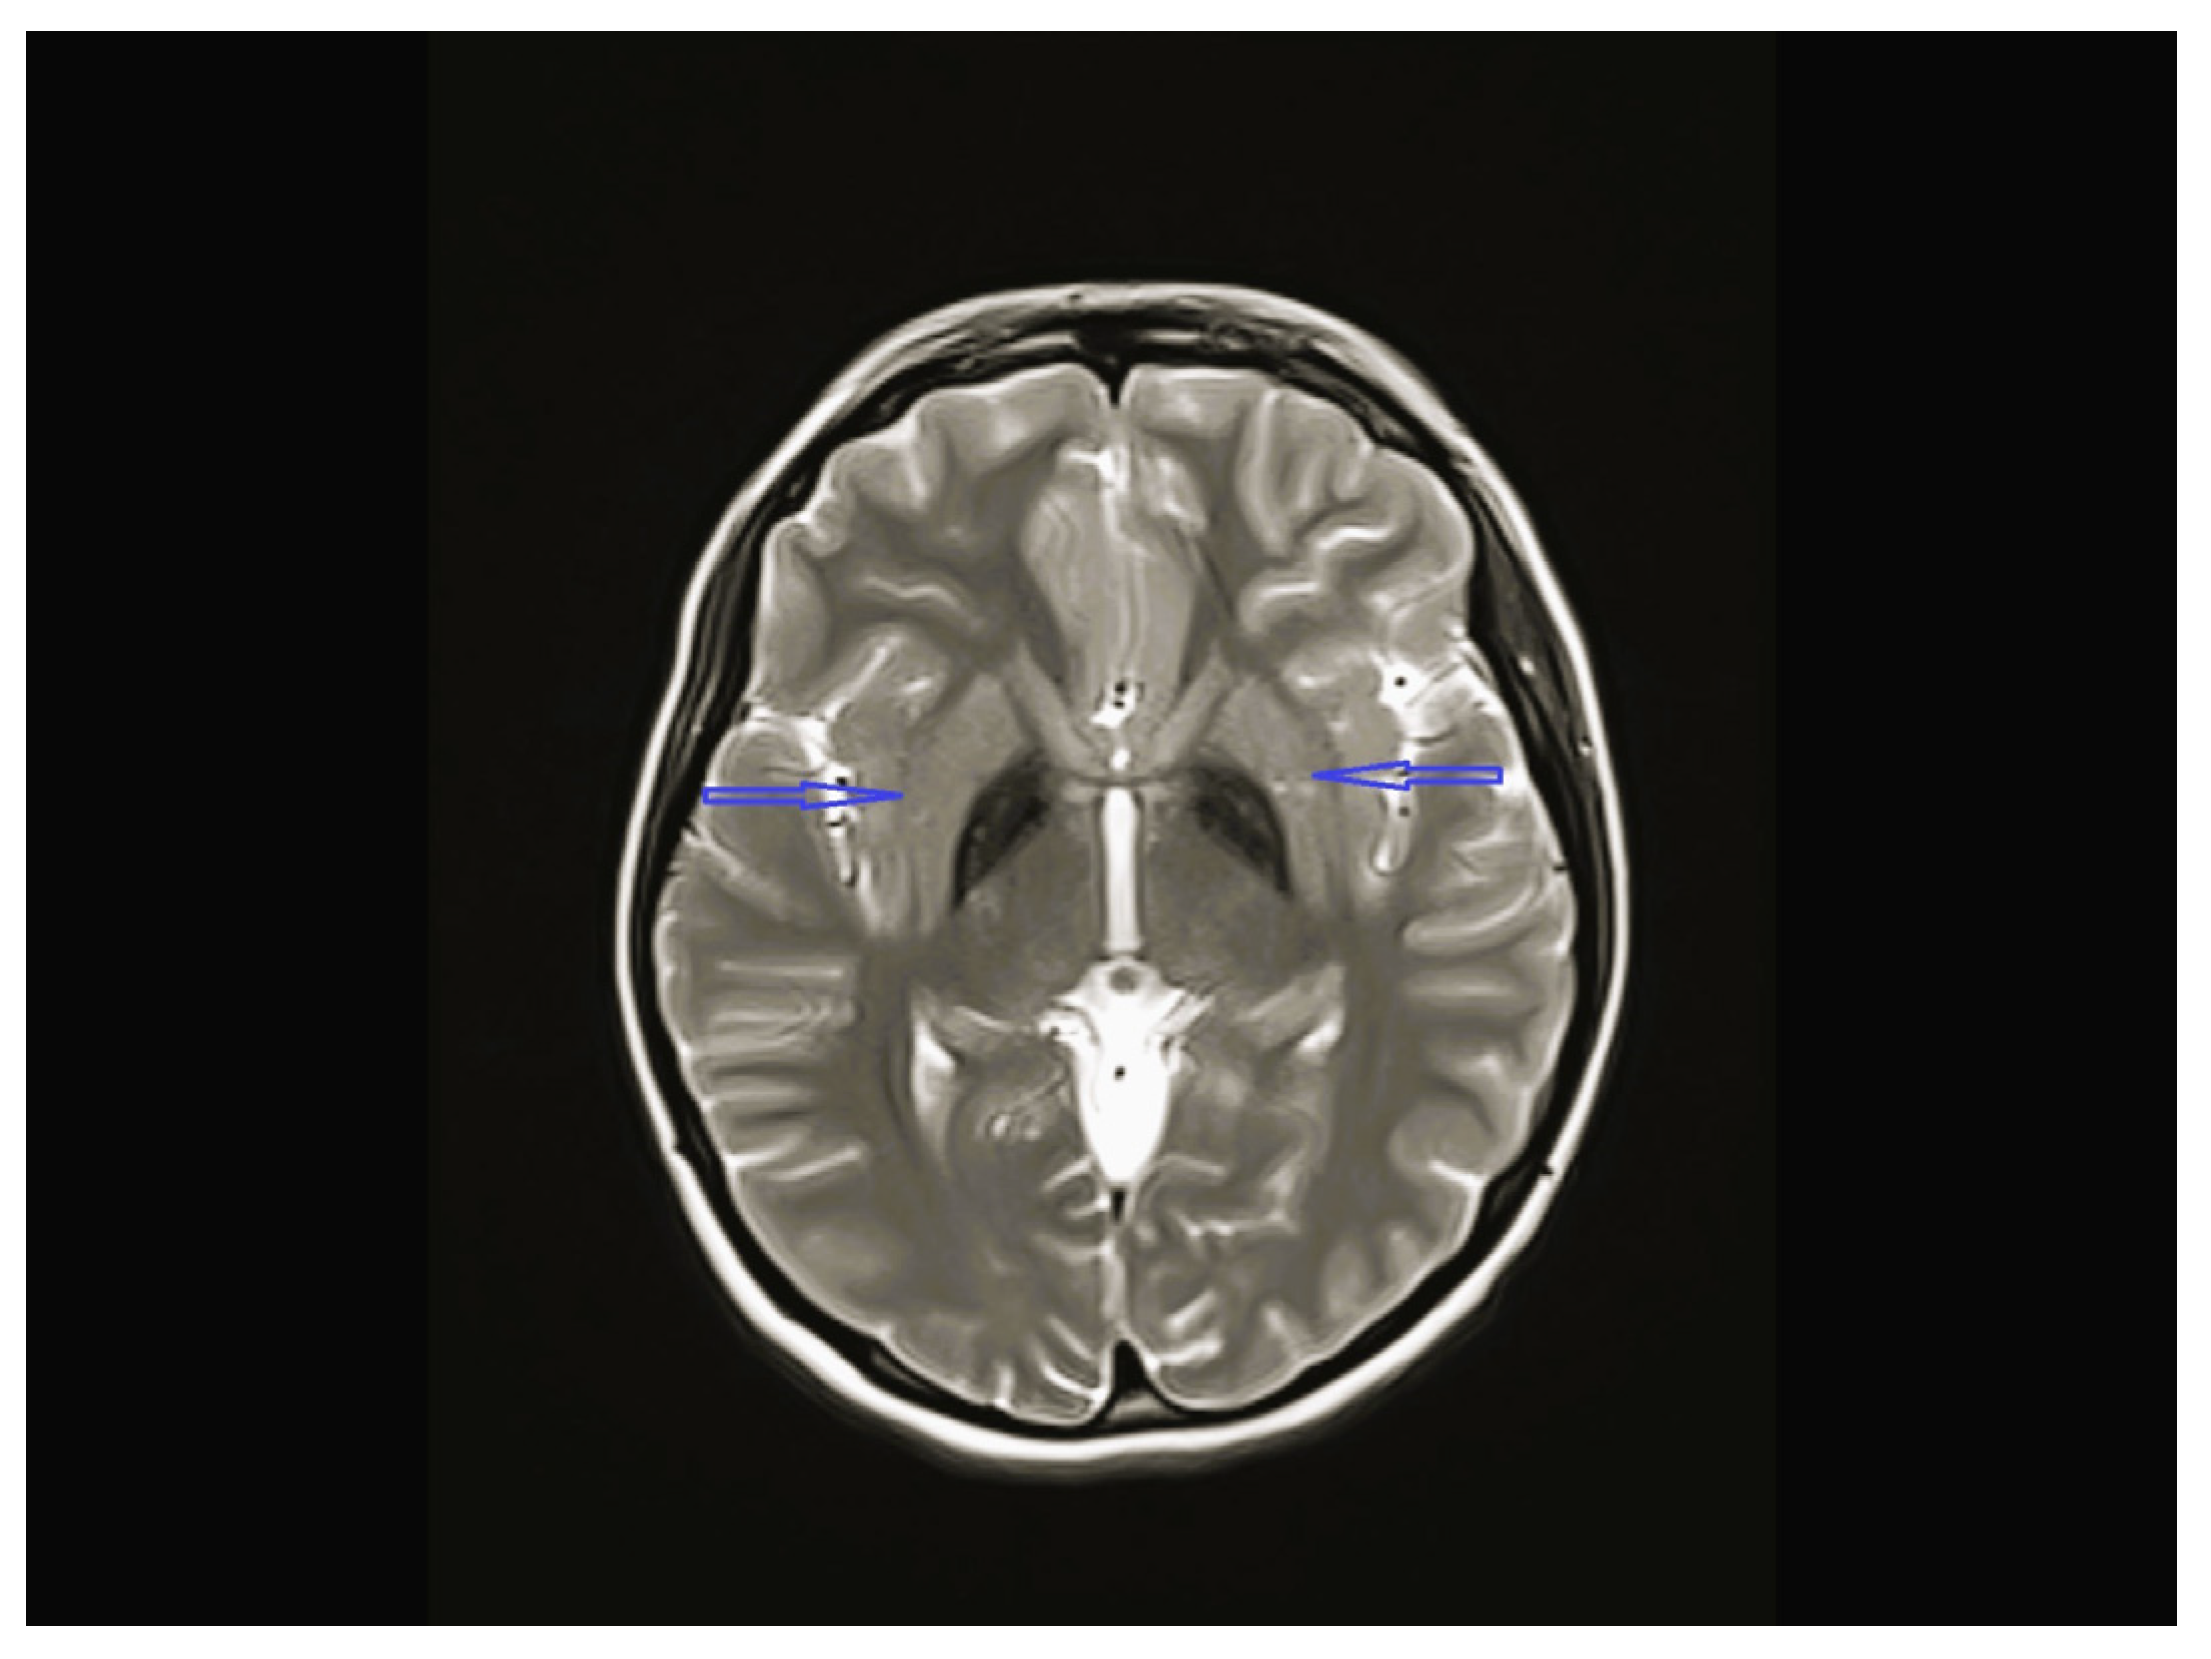

| 4 | Normal | Normal | Normal | Bilateral globus pallidus T2 hypointensity and iron accumulation | - | C19orf12c.385C>T (p.Q1239*)(p.Gln129Ter) Homozygote  | Physical therapy, carbidopa/levodopa, baclofen, |